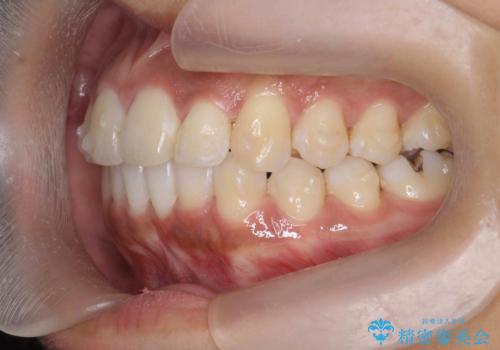

出っ歯感のある前歯を治したい、抜歯をしないマウスピース矯正

- 前歯のガタつき、突出感のある前歯の改善を求めて来院されました。

前歯の角度を改善し審美性を高めるとともに、奥歯のガタつきも並べ直すことで安定した咬合関係の確立を目指します。

歯列の側方拡大をしっかりと行ったことで歯を抜かずに前歯の角度をしっかりと改善することができました。